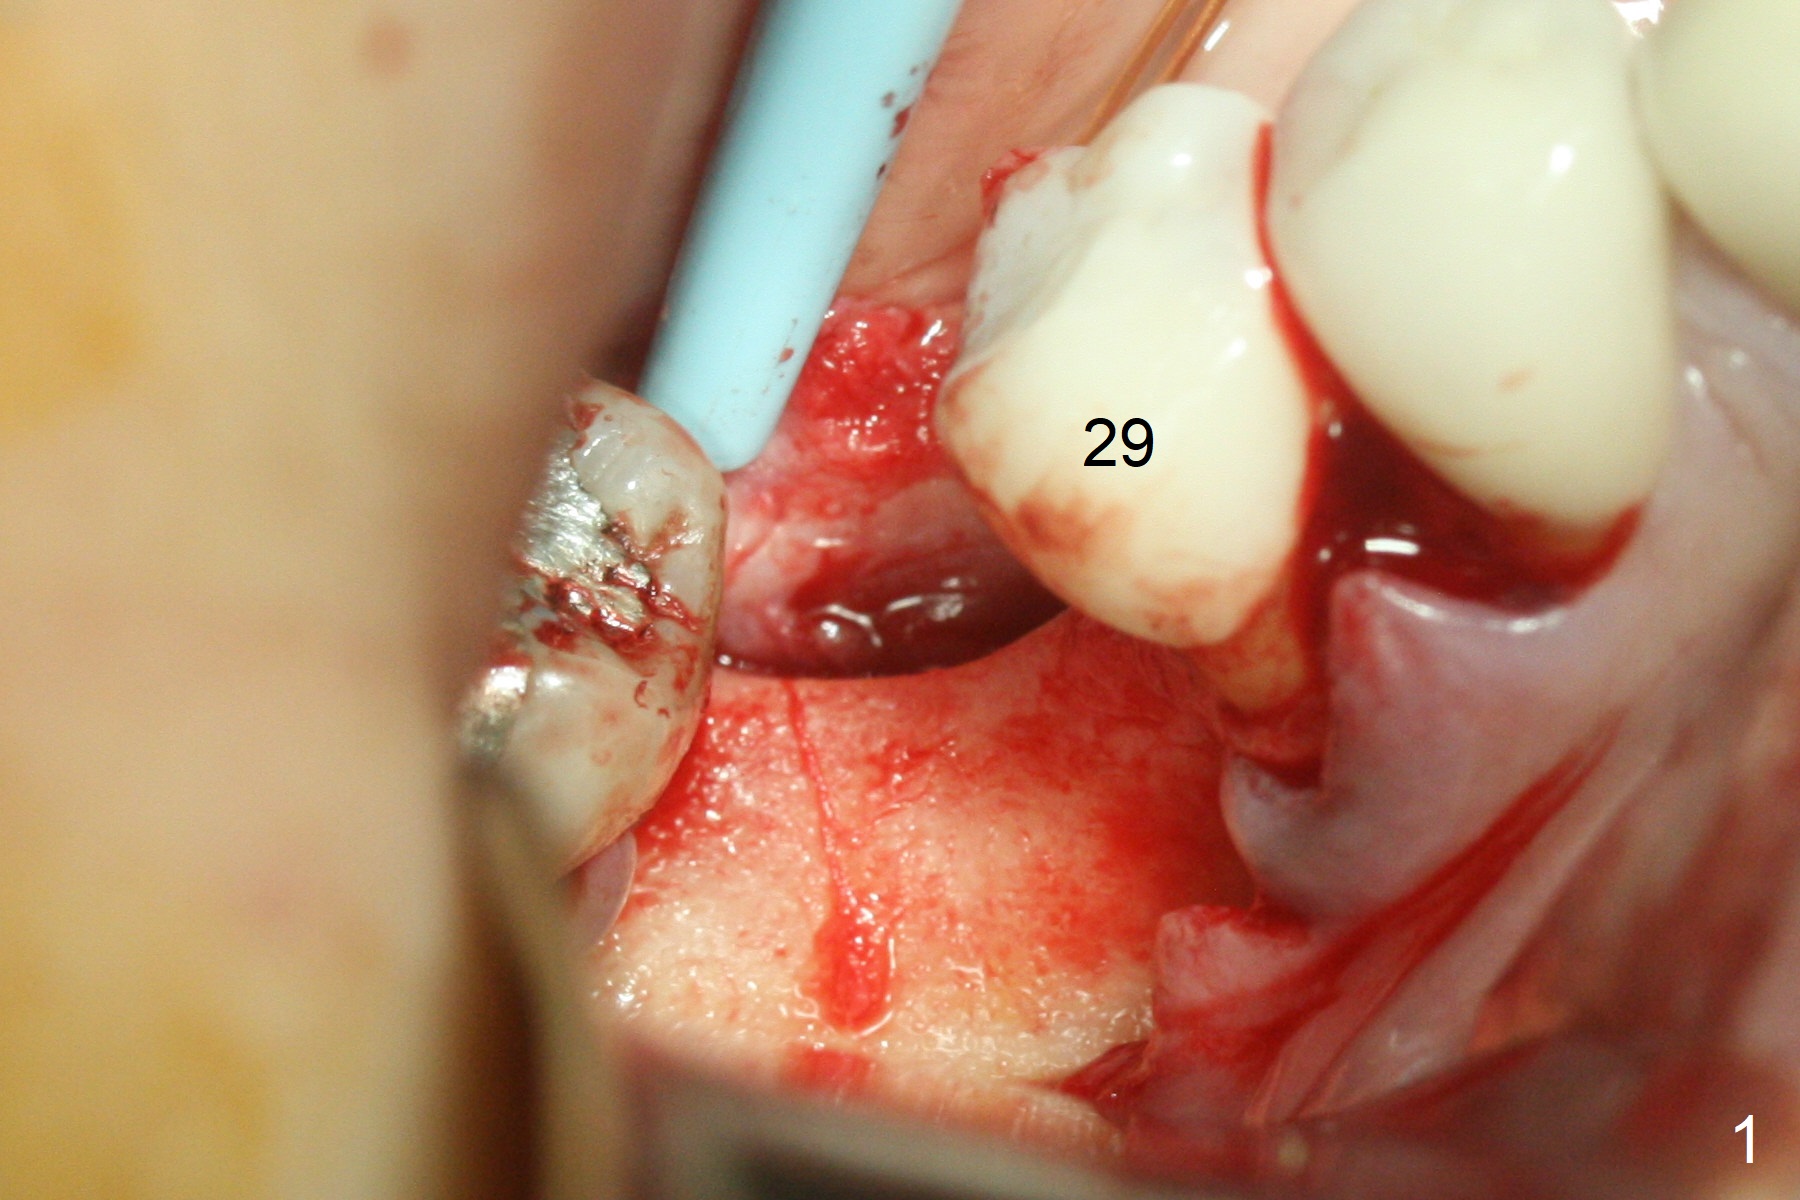

Incision reveals a narrow ridge and a narrow mesiodistal space at #30 (Fig.1).  It seems that a 1-piece implant is indicated.  Due to limited mouth opening, a 1.2 mm drill is unstable in place after use for 10 mm; instead a 1.5 mm drill is able to be inserted for 8 mm (Fig.2).  A 3x10(2) mm 1-piece dummy implant is placed with 40 Ncm at an apparently acceptable level (Fig.3 >).  Clinically a few threads are exposed buccally.  When a definitive implant with the same dimension is inserted with 45 Ncm, it looks seated too deep (Fig.4,5).  The latter is noted after suturing.  The implant is backed up for a few turns so that the length of the abutment appears a little more reasonable.  Introspectively, a 4 mm cuff should have been used after ridge reduction.  Although there is no bone loss 4 months postop (Fig.6), the abutment margin (Fig.7 arrow) is subgingival (red dashed line: gingival margin).  Diode laser is used for gingivectomy prior to impression.  The bone density around the implant increases 11 months post cementation (Fig.8 *), probably related to recurrent #18 infection.  The patient uses floss after meal.